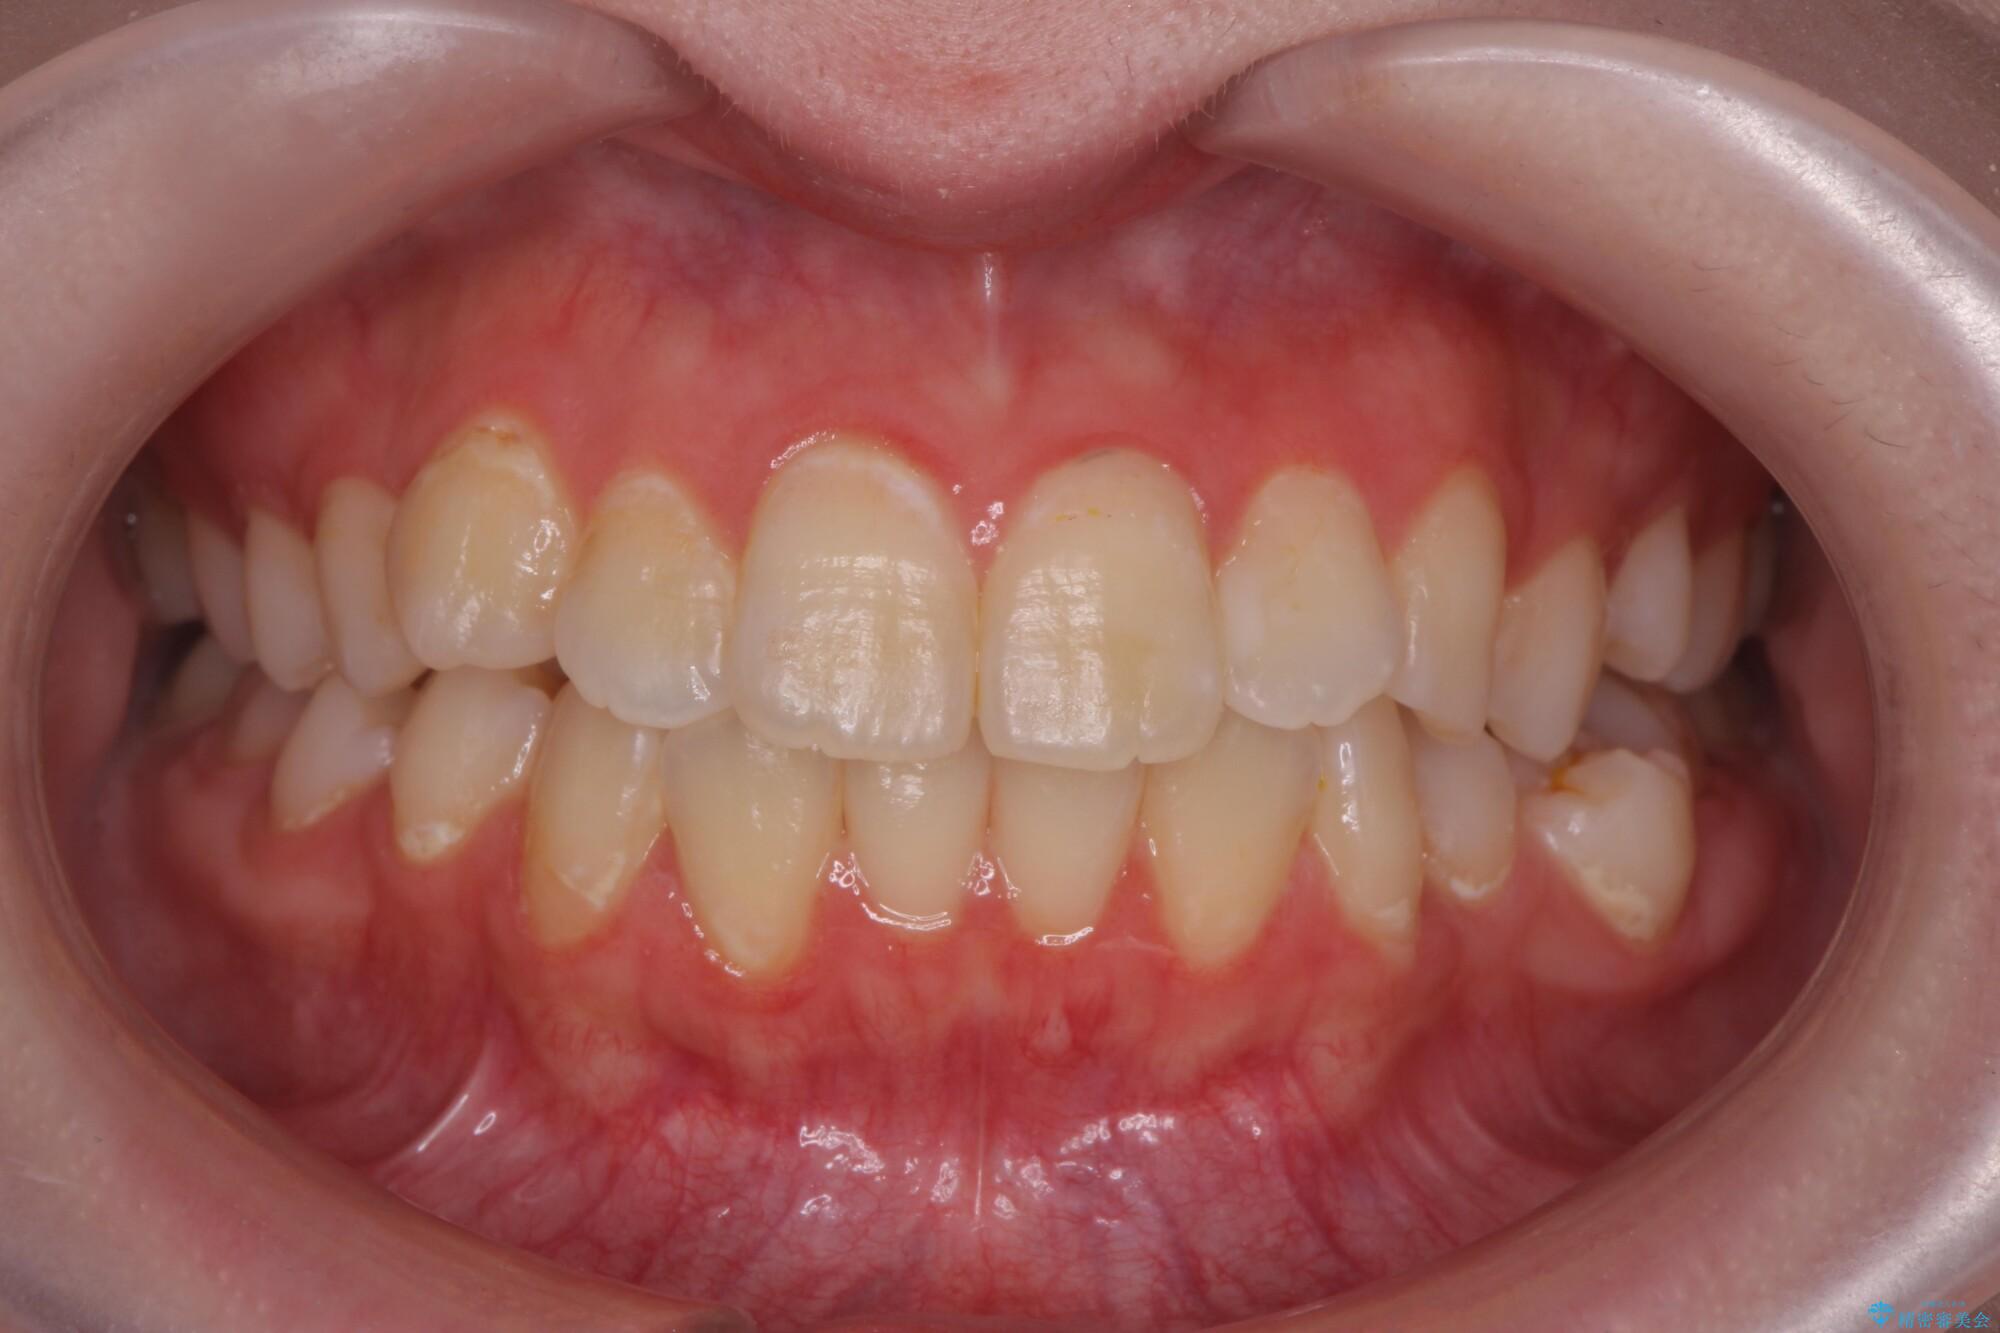

治療前

奥歯のガタつきをマウスピース矯正で改善 治療前画像 奥歯のガタつきをマウスピース矯正で改善 治療前画像 奥歯のガタつきをマウスピース矯正で改善 治療前画像

治療後

奥歯のガタつきをマウスピース矯正で改善 治療後画像 奥歯のガタつきをマウスピース矯正で改善 治療後画像 奥歯のガタつきをマウスピース矯正で改善 治療後画像